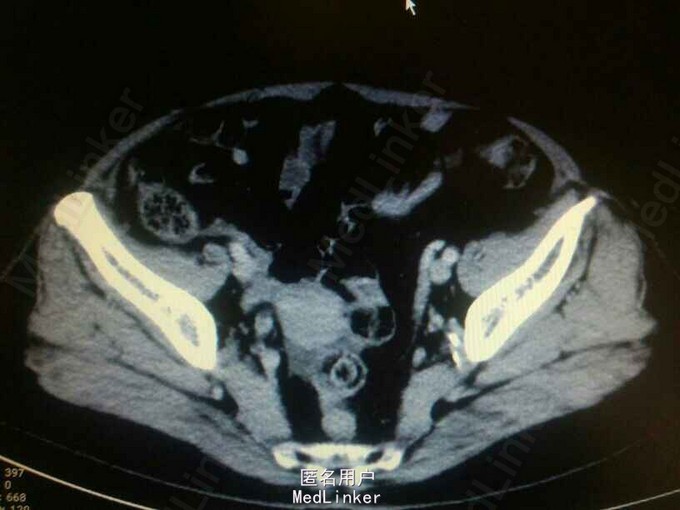

查体:无明显阳性体征! 辅助检查:CTU提示:右侧输尿管下段占位?输尿管镜检,右侧输尿管下段新生物,约1*1cm,病检示高级别浸润性尿路上皮癌?

右侧输尿管下段癌